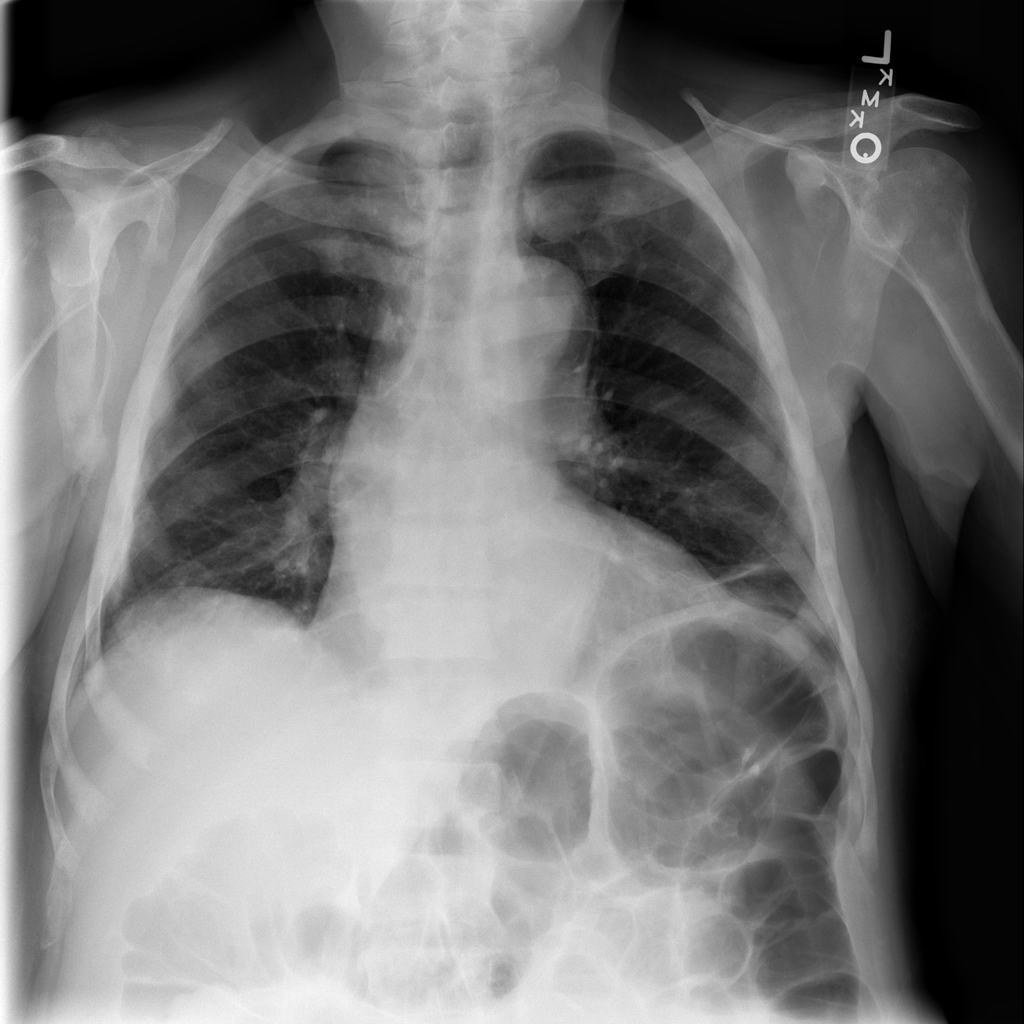

PAT-DB80 · IMG-001Atelectasis

PAT-DB80 · IMG-001

PA